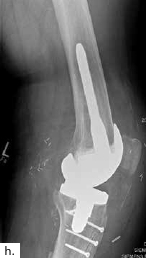

Ein 28-jähriger Motorradfahrer kollidierte mit einem Pkw und erlitt eine Defektfraktur der linken proximalen Fibula und einen Verlust der lateralen Femurkondyle inklusive des lateralen Bandapparates unter einem extrem großen Weichteildefekt (Abb. 2a u. b). Nach multiplen auswärtigen Debridements wurde nach Zuweisung ins eigene Haus interdisziplinär besprochen, die Extremität mit einer Kniegelenkprothese und einer plastisch-chirurgischen Defektdeckung zu erhalten. In einem ersten Schritt wurde ein kontralateraler Tensor-fasciae-latae-(TFL-) Lappen umschnitten („flap delay“), um ihn in seiner gesamten Länge vom Beckenkamm bis zum Knie heben zu können. Eine Woche später erfolgte die Konstruktion der fabrizierten Chimärlappenplastik durch Hebung des osteofasziokutanen TFL-Transplantats inklusive eines vaskularisierten Beckenkammblocks und der mikrovaskuläre Anschluss End-zu-End an den Serratusabgang der A. thoracodorsalis des rechten muskulokutanen M.-latissimus-dorsi-Lappens (Abb. 2c). Dieses sehr große zweiblättrige Lappenmodul wurde anschließend End-zu-End an die Vasa gastrocnemia lateralis anastomosiert und die vaskularisierten Einzelkomponenten wie folgt verteilt: Der Beckenkammblock fungierte als laterale Kondylenaugmentation, um den Sitz einer späteren Knieendoprothese zu optimieren; die Faszia lata wurde zur Stabilisierung von diesem Block transossär an die verbleibende Fibula und das laterale Tibiamassiv genäht (Abb. 2d). Die ausgedehnten Lappenplastiken dienten zum Defektverschluss, gemeinsam mit zusätzlichen Spalthauttransplantaten (Abb. 2e). Nach sechswöchiger Abheilung im Fixateur externe erfolgten der Umschulungsbeginn und die Mobilisation an Unterarmgehstützen mit Fußsohlenteilkontakt.

Sechs Monate später konnte bei solide eingeheiltem Knochenblock (Abb. 2f) eine teilgekoppelte Kniegelenkprothese implantiert werden, deren Bedeckung in der Folge durch die ausreichend dimensionierten Lappenplastiken unproblematisch war (Abb. 2g u. h). Der Patient erzielte nach Rehabilitationsmaßnahmen eine vollständige Belastungsfähigkeit bei freier Kniegelenkbeweglichkeit und solide verheiltem Integument (Abb. 2i u. j).